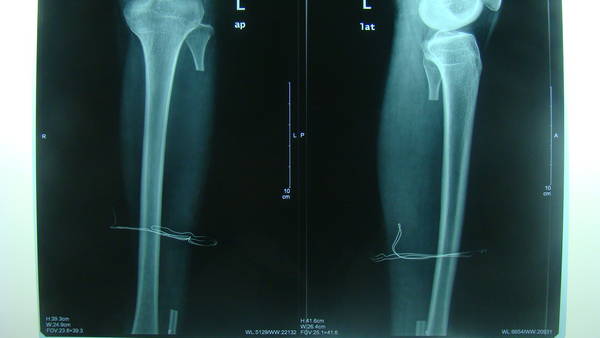

[修复重建] 游离腓骨移植术

补发术前术后照片